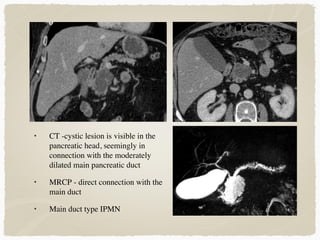

• CT -cystic lesion is visible in the

pancreatic head, seemingly in

connection with the moderately

dilated main pancreatic duct

• MRCP - direct connection with the

main duct

• Main duct type IPMN